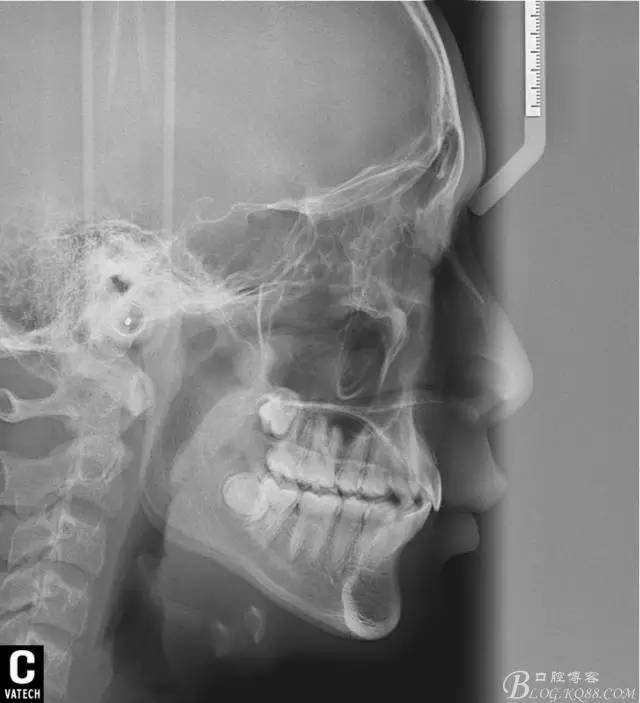

術(shù)后全景,側(cè)位照。

幾何畫板技術(shù)完成術(shù)后頭影測量!